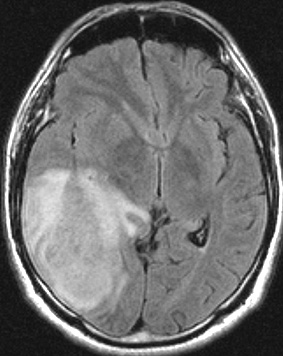

左がガドリニウム増強像で,手術ではこの部分が取れれば全摘出といわれるのですが,実際は右側のフレア画像で白っぽく見える所には腫瘍が滲み込んでいます。この部分を全て摘出してはじめて,画像上の全摘出といいます。全摘出は無理でしょう